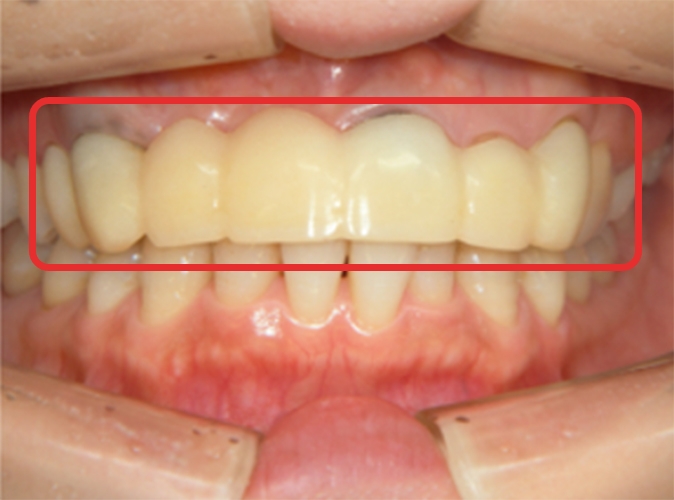

Cさん

自然な歯を求める方

大学時代にモデル事務所から前歯を整えるように言われ、神経を抜く手術を受けました。あまりの痛みに治療を続けられず放置してしまい、抜歯に。

前歯数本が仮歯の状態なのをずっと気にしていたところ、歯科衛生士の母のかかりつけ医院である川越歯科医院がインプラントをしていると聞き、来院しました。

治療概要

| ご希望 | 自然な前歯を入れたい。 |

|---|---|

| 治療内容 | 長い間仮歯の状態。インプラントを埋め込み、天然歯のような自然な仕上がりを目指す。 前歯2本を抜歯し、同時に3本のインプラント埋入とGBR(歯槽骨を再生する治療)を行う。長い治療期間でも生活の質を保つために、口腔内の状況に合わせた仮歯を装着。 |

| 治療期間・回数 | 1年~1年6ヶ月・10~15回(仮歯の調整に回数がかかります。) |

| 費用 | 200万円 〜 250万円 |

| 想定されるリスクと副作用 | 1~2週間の痛み、腫れ、内出血。 |

手術を終えて

笑った時に自然な口元になりたいという思いでお願いしました。母が「何とかなりませんか?」と相談した際も「治療期間が長くなるけれど、時間をかけてでも綺麗な仕上がりになるようなんとかします」と私に合った方法を考えてくれました。

先生から一言

術後、泣いて喜んでくださったのを覚えています。笑った時のスマイルラインも自然で、人工歯には思えません。天然歯かインプラントか、歯医者さんが見ても分からないと思います。